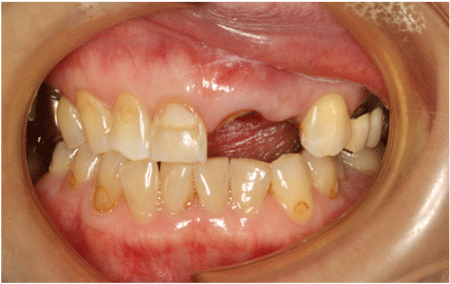

2024.08.1750代女性「前歯が2本折れてしまった」インプラントとジルコニアの補綴で治療した症例